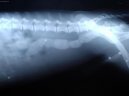

Psí plemena:  > Cizí tělesa v zažívacím traktu a kostní trus. (Veterinární zákroky) Cizí tělesa v zažívacím traktu a kostní trus. (Veterinární zákroky) - Cizí tělesa jsou jednoduše takové předměty v zažívacím aparátu, které tam zkrátka nepatří.